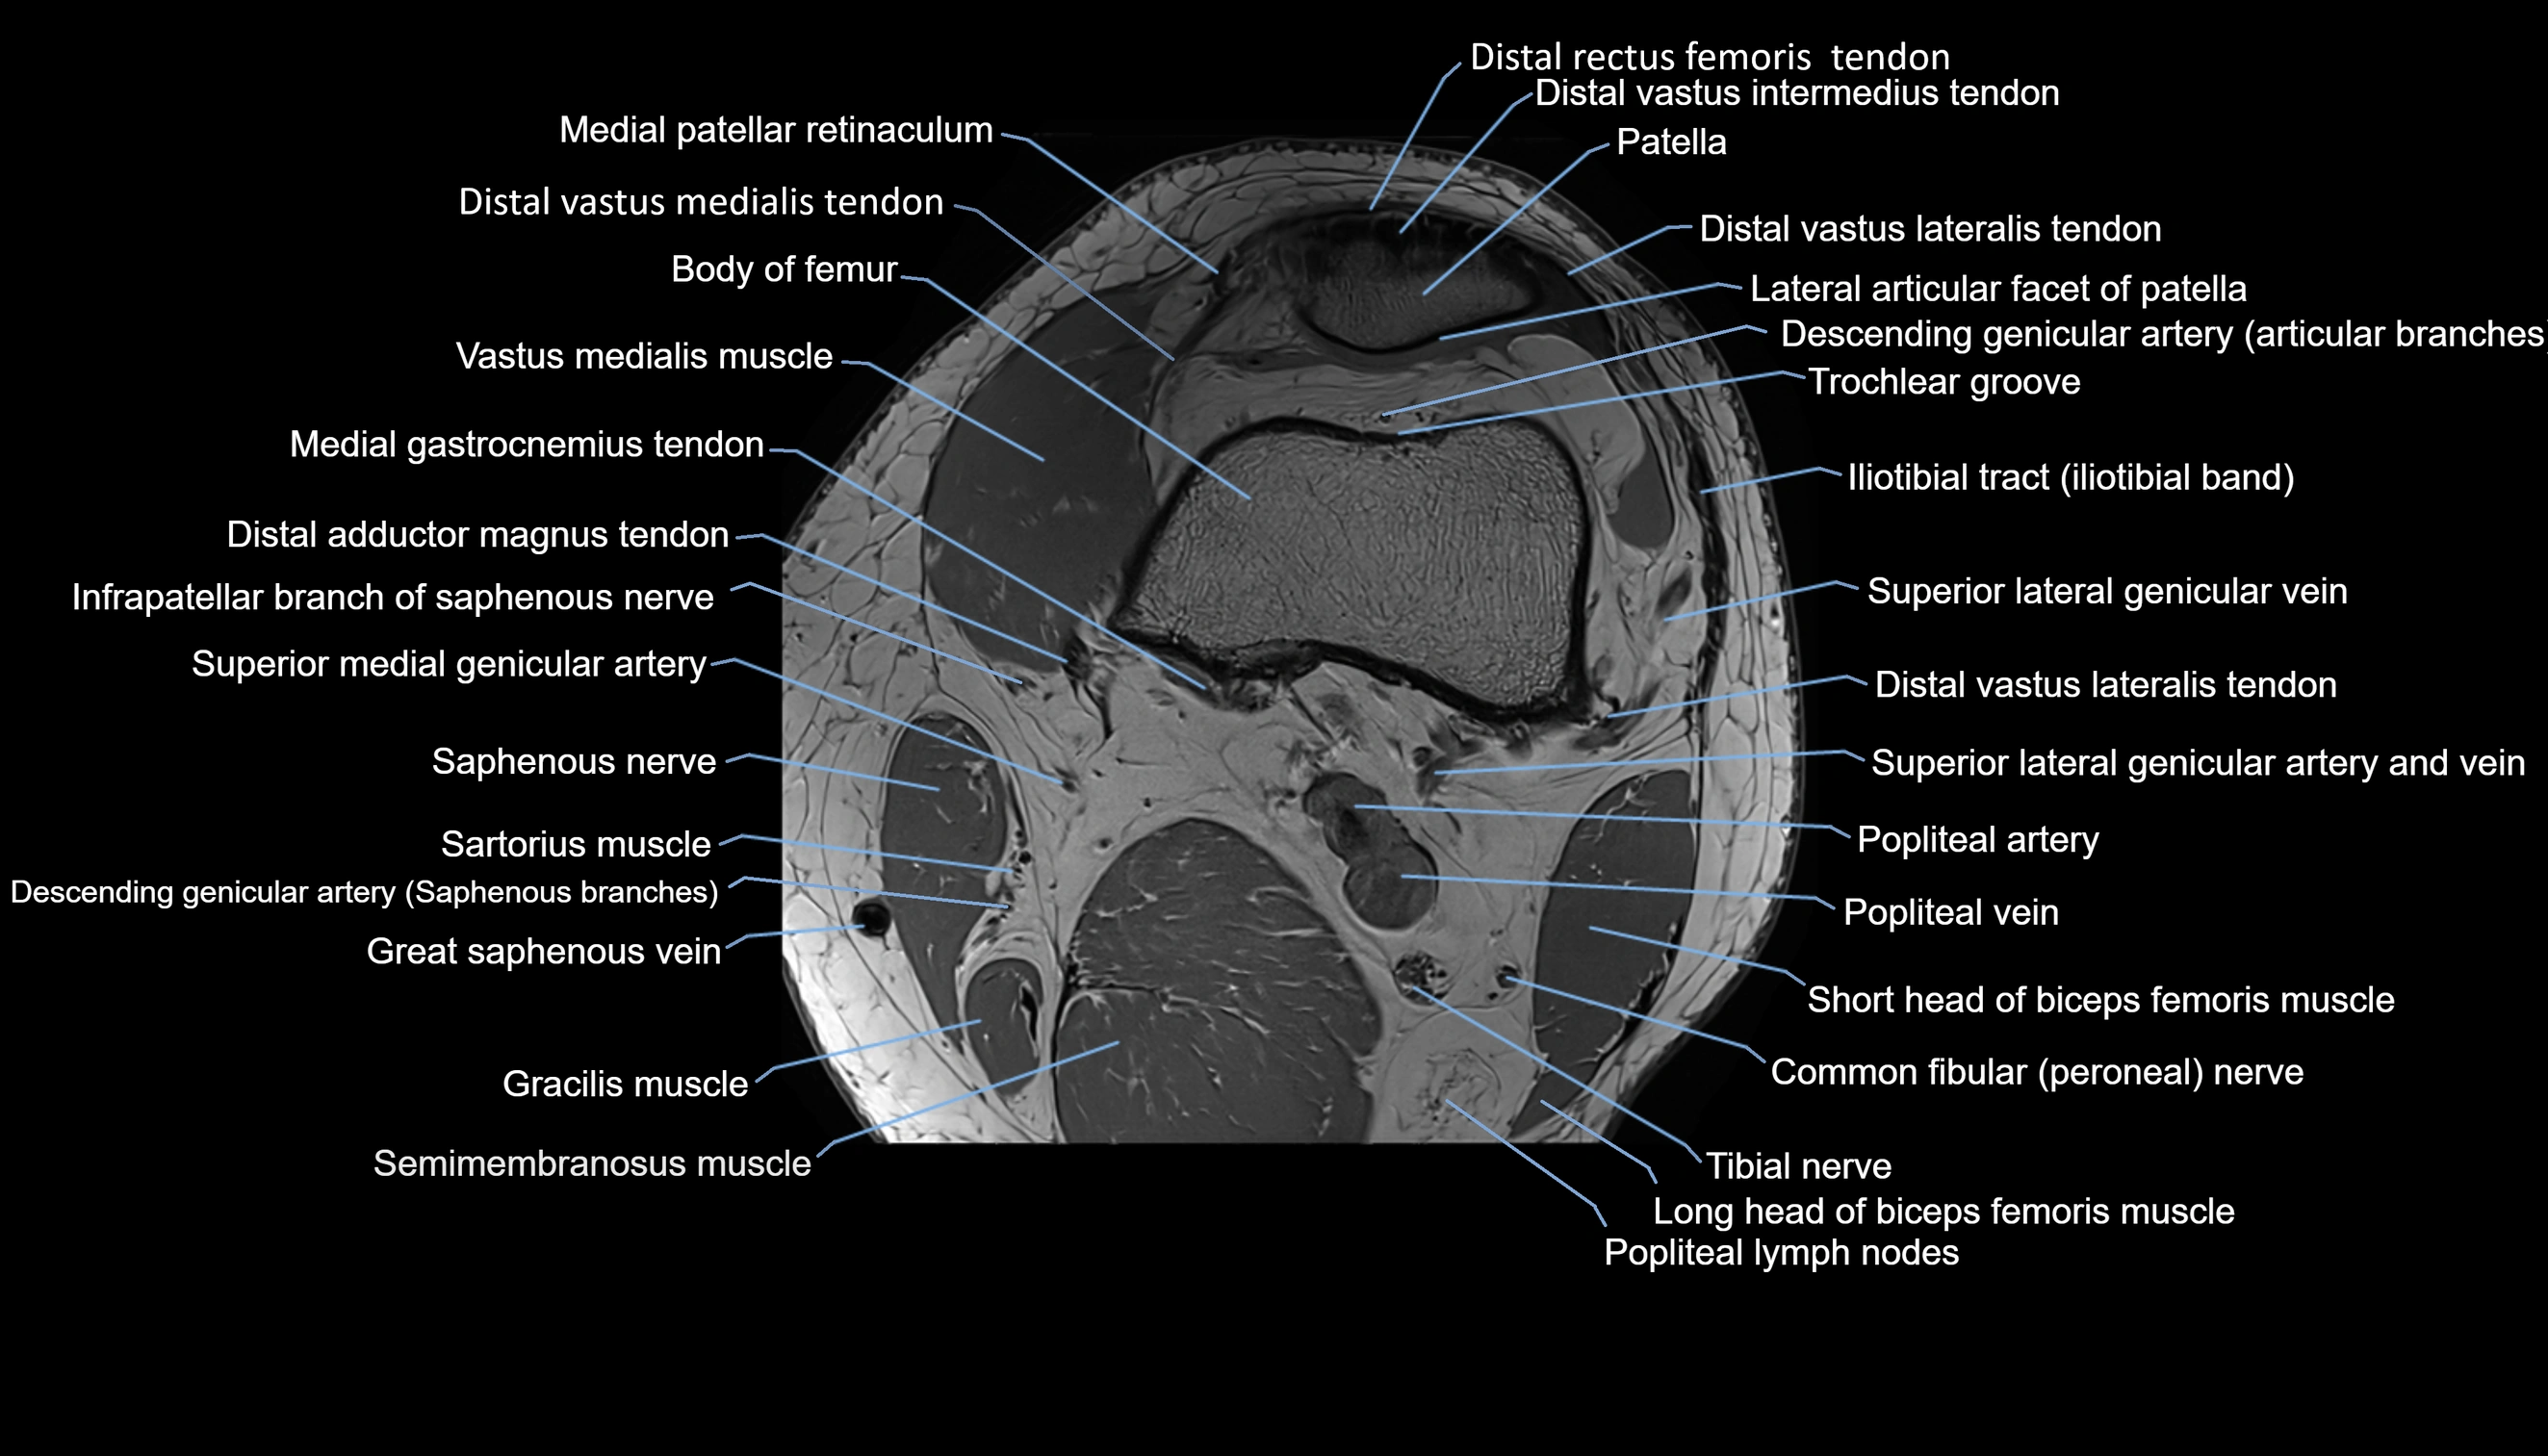

- Descending genicular artery (Articular branches)

- Descending genicular artery (Saphenous branch)

- Infrapatellar branch of saphenous nerve

- Popliteal artery

- Popliteal lymph nodes

- Popliteal vein

- Saphenous nerve

- Sartorius muscle

- Tibial nerve

- Trochlear groove

- great saphenous vein